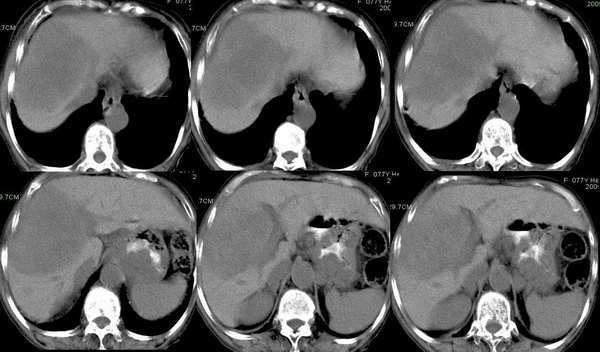

动脉期

可以肯定为肝癌;首先要指出的是,这个病例的三期扫描不规范,动脉期时间太早了,而门脉期的表现却是动脉期的表现,肾脏皮髓质交界清晰,说明处在动脉期但又略晚了点,看肝癌表现,以动脉晚期最为可靠,即动脉显影明显,脾脏呈花斑样强化,门脉初步显影,此表现为诊断肝癌最可靠的时期。这个病例肝脏有硬化表现,合并腹水,增强后病灶明显强化且边界不清,肝动脉异常增粗,门脉右支受侵,右后叶也有一处小病灶,为子灶。我的诊断为:肝右叶原发浸润型肝癌,肝硬化,门脉高压,腹水。下肢浮肿,可能为下腔静脉癌栓形成。